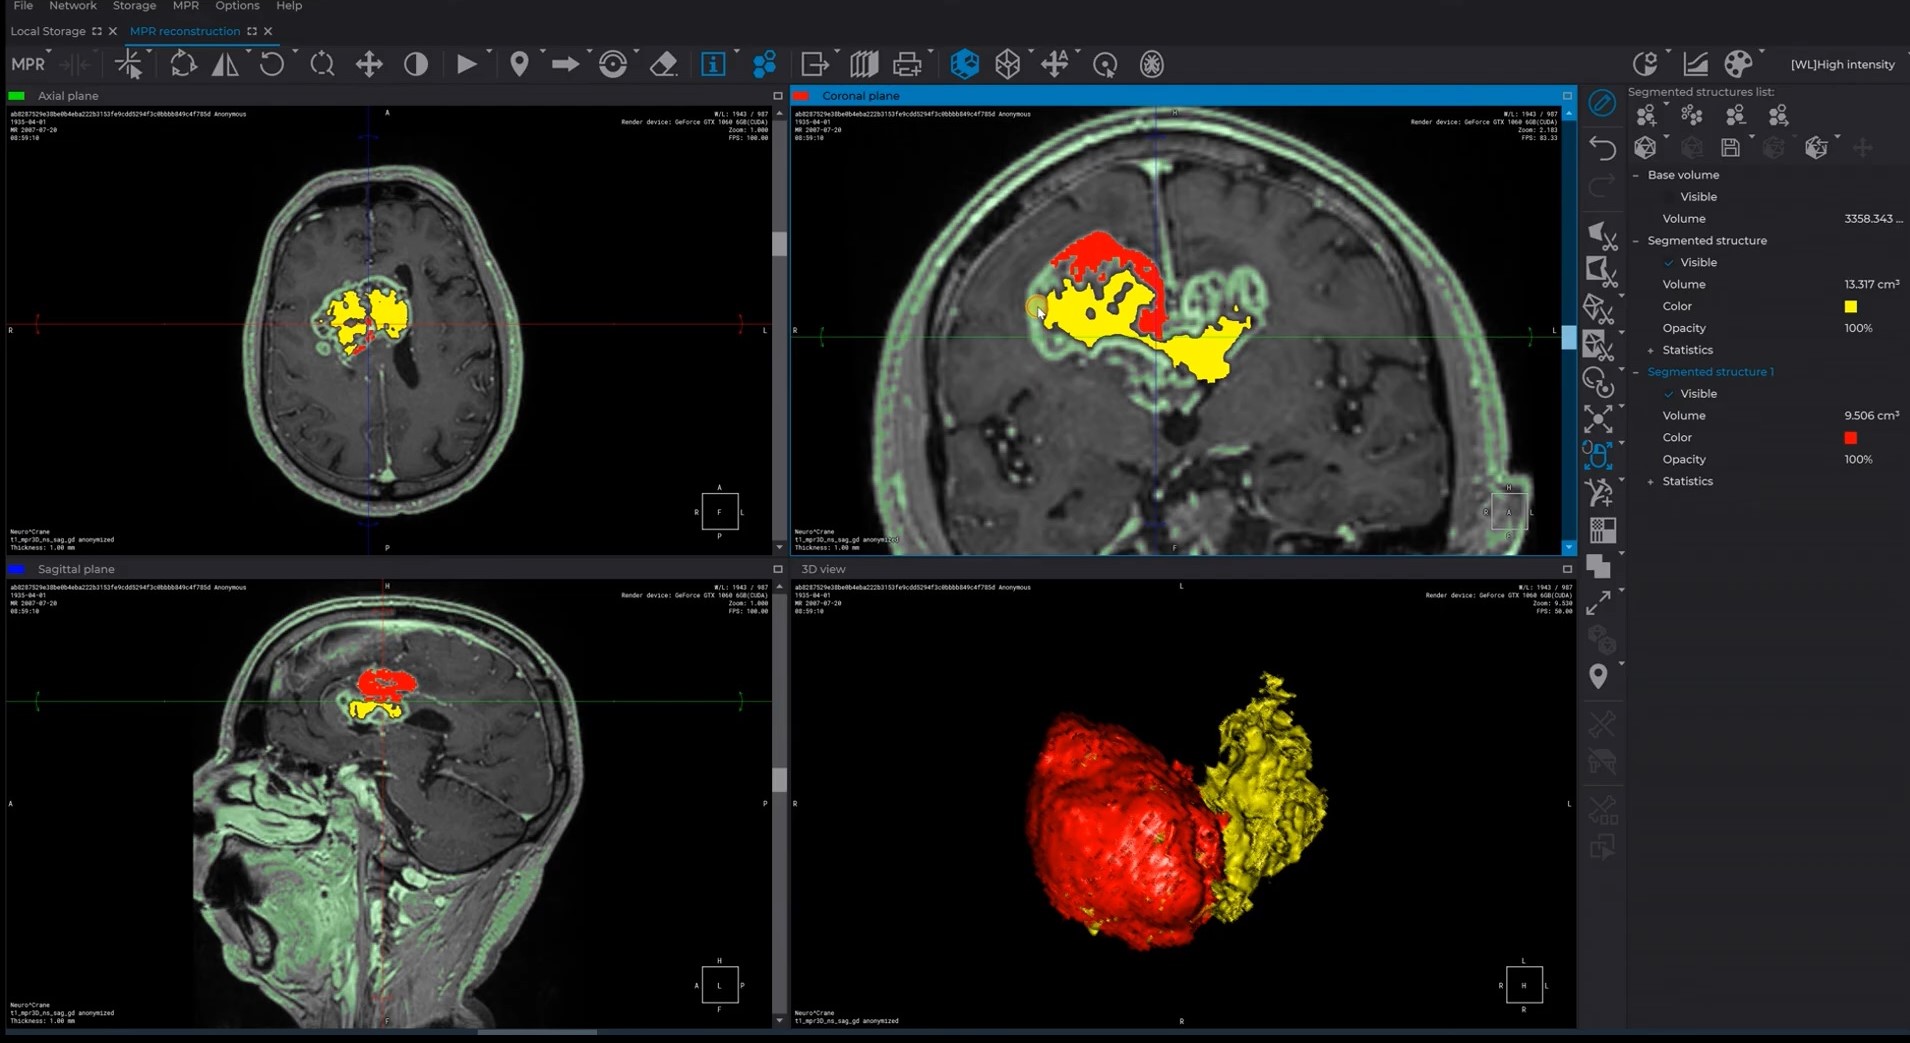

Advanced capabilities for working with 3D reconstructions

Advanced multiplanar reconstruction capabilities